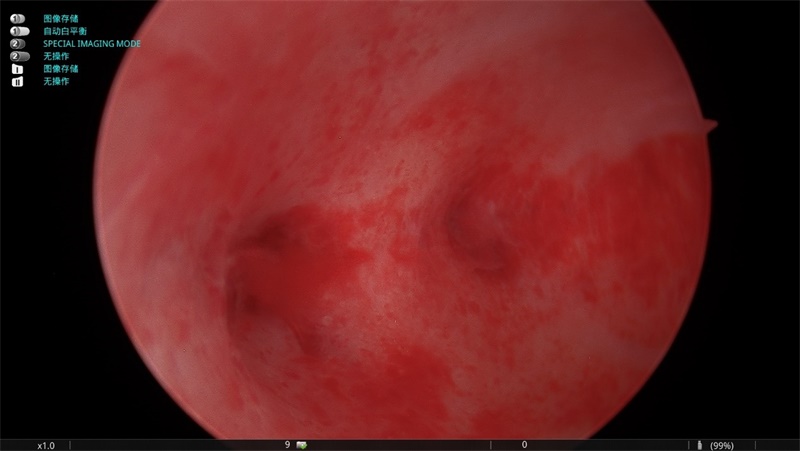

患者长期以来阴道不规则出血,严重影响日常生活,曾多次检查均未能查明病因。得知南大一附院与井冈山医院结成紧密型医联体,医生、护士、麻醉师都是南大一附院高年资工作人员,管理、医疗、护理同质化运行,故前来求治。为了打消患者的顾虑,医联体副院长陶利民组织妇产科医务人员针对患者病情进行个体化分析,确定了宫腔镜的手术方式。手术中发现患者宫颈管及宫腔粘连严重,陶利民沉着应对,细心操作,将粘连组织完全分离,恢复宫腔的正常解剖形态并成功切除息肉。